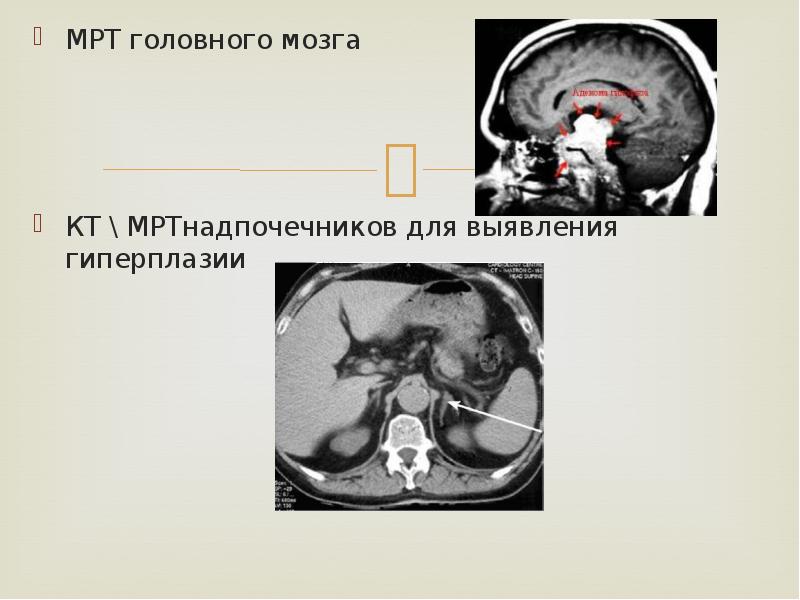

МРТ головного мозга

МРТ головного мозга

КТ МРТнадпочечников для выявления гиперплазии